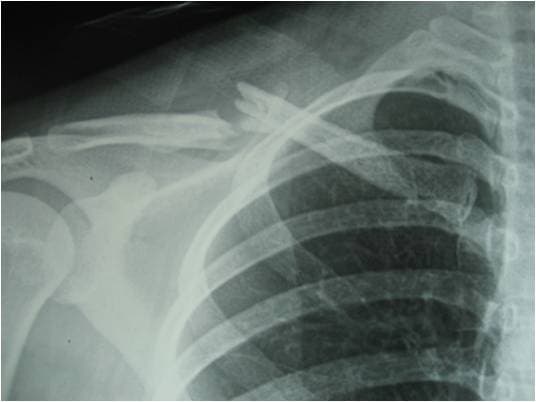

Xương đòn hay xương quai xanh là xương ở phần vai và ngực cấu thành, có vai trò trong sức mạnh vai – cánh tay và yếu tố thẩm mỹ. Gãy xương đòn là tình trạng chấn thương ở bộ phận này và thường gặp với đoạn 1/3 giữa. Những biểu hiện gãy xương đòn bao gồm:

Gãy xương đòn là tình trạng chấn thương ở bộ phận này và thường gặp với đoạn 1/3 giữa

Phẫu thuật gãy xương đòn là sử dụng các phương tiện để nối phần xương đã gãy về tình trạng ban đầu tạo điều kiện cho xương hồi phục. Phương pháp này áp dụng cho bệnh nhân với đường gãy quá mức phức tạp, gãy dài hoặc di lệch nhiều chồng ngắn trên 2cm đe dọa tổn thương mạch máu.

Phương pháp này được điều trị với: đóng đinh nội tủy hoặc KHX bằng nẹp vít. Để được chỉ định phương pháp phù hợp cần phụ thuộc vào nhiều yếu tố.

Trong đó nếu trong lòng tủy bệnh nhân đường gãy không thành nhiều mảnh thì có thể đóng đinh. Tuy nhiên nhược điểm là dễ lộ đinh khi chúng chưa chắc vào xương. Bên cạnh đó, đường mổ thường nhỏ và đơn giản.

Đối với nẹp vít đường mổ thường dài hơn nhưng sẽ nắn vững và tuyệt đối hơn.